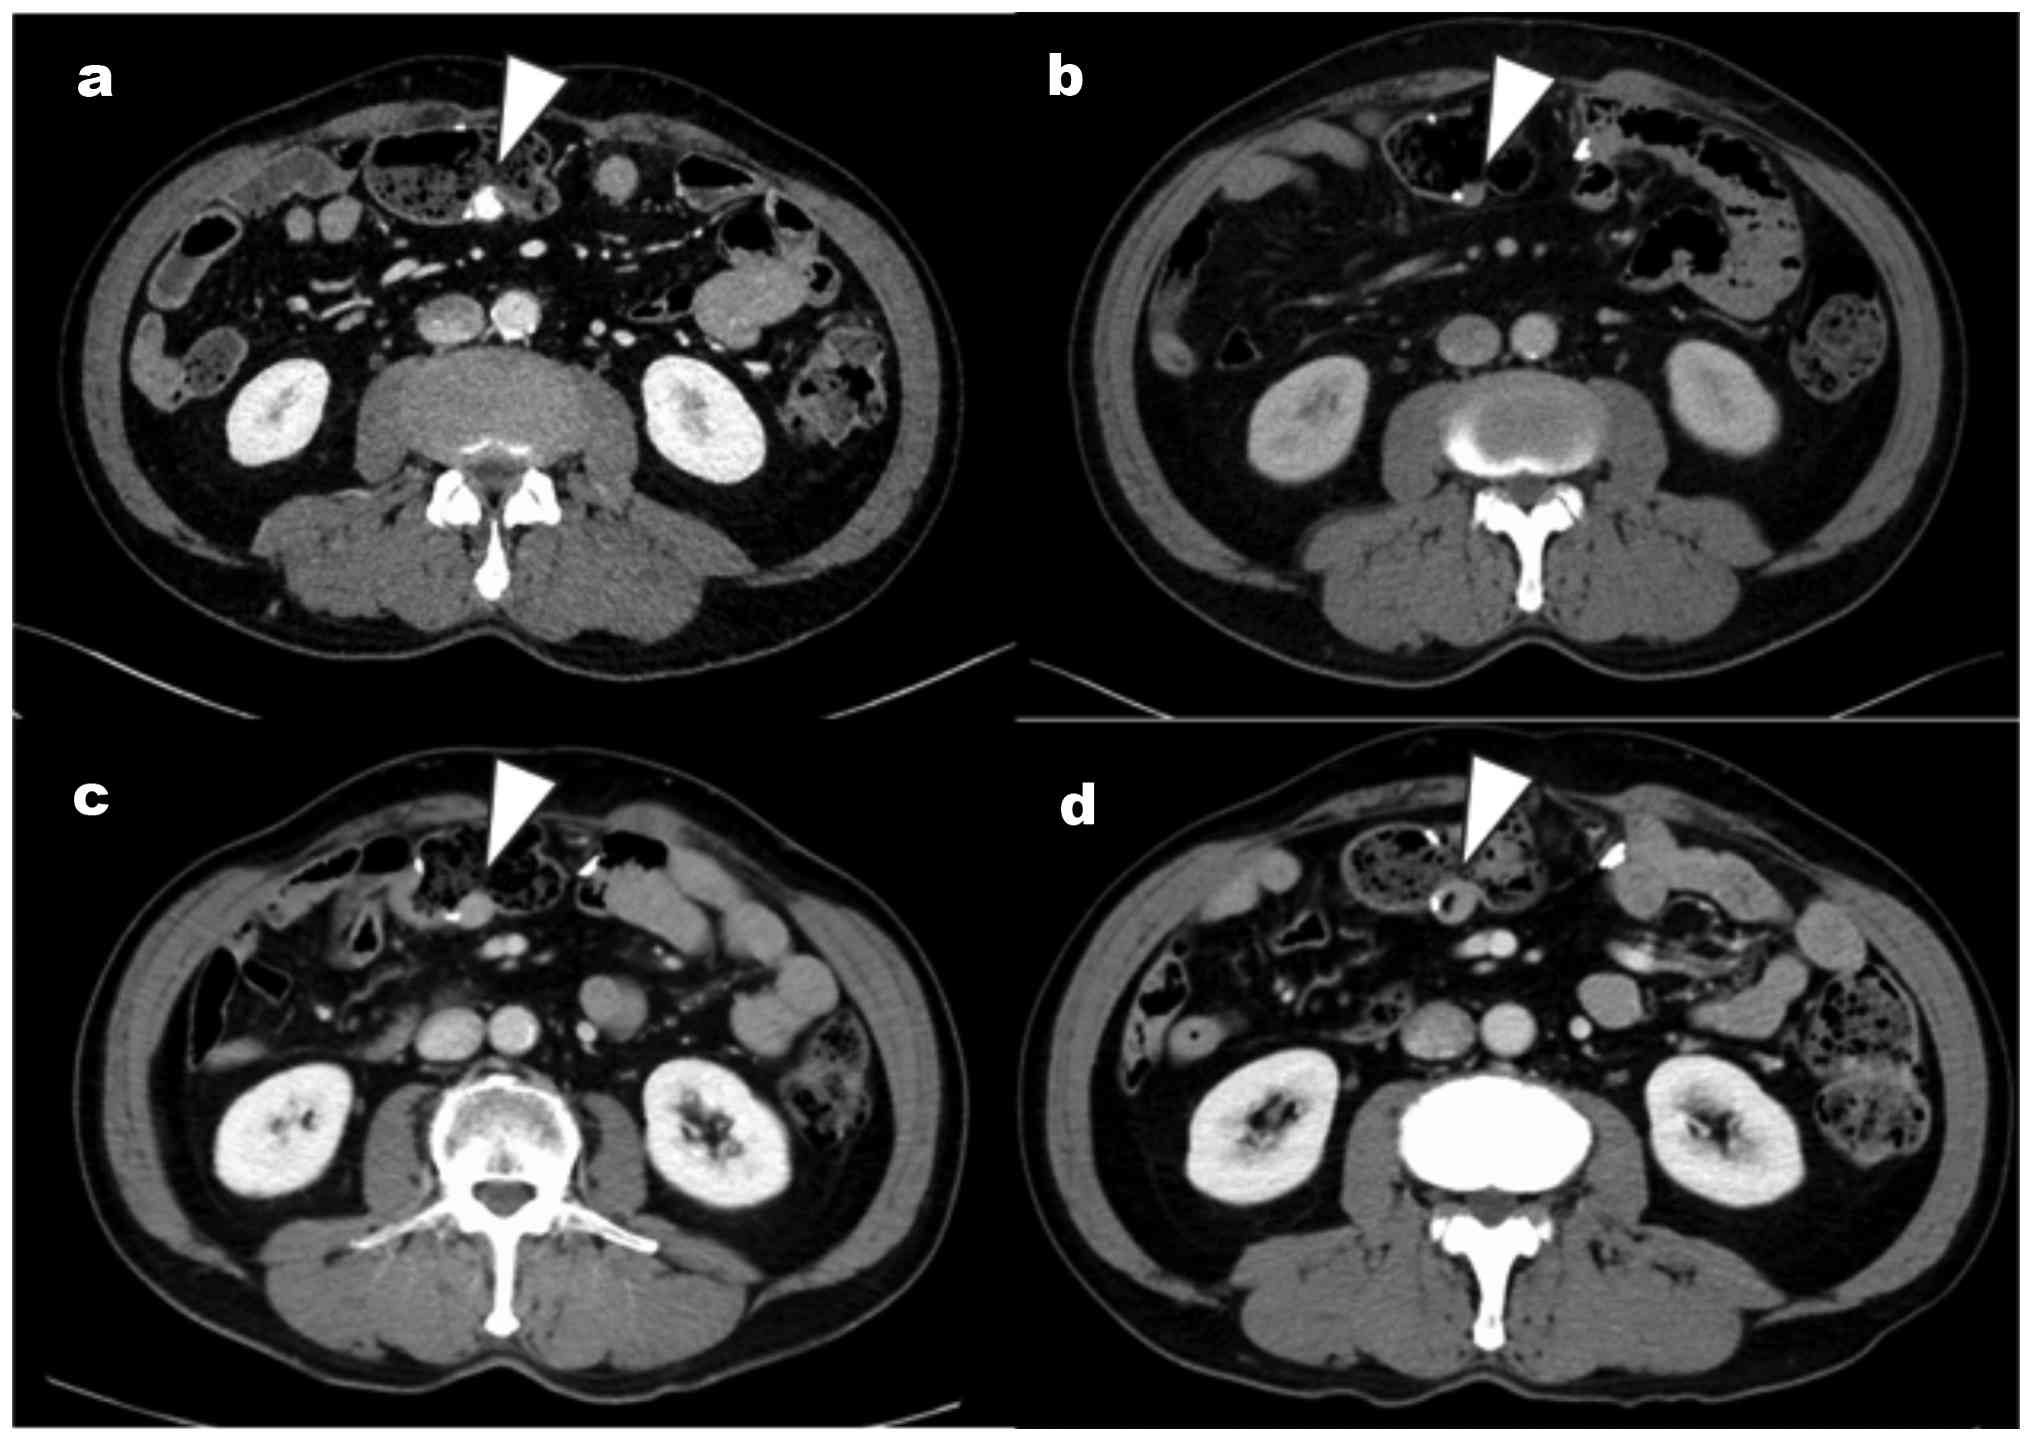

Contrast-enhanced CT findings. (A)

Contrast-enhanced CT 1 year after GIST surgery (3rd surgery; 11

years after the 1st surgery) showed a calcified submucosal lesion

at the anastomotic site following transverse colectomy (arrowhead).

The nodular lesion (arrowhead) was first identified (B) one year

after the 1st surgery following the retrospective review of CT

images, and (C) an increase trend in size five years after the 1st

surgery. (D) Nine years after the 1st surgery, the lesion

(arrowhead) continued to enlarge, with visible air. The order of

the figures in the actual time series is b, c, d and a. CT,

computed tomography.

Figure 1

Contrast-enhanced CT findings. (A) Contrast-enhanced CT 1 year after GIST surgery (3rd surgery; 11 years after the 1st surgery) showed a calcified submucosal lesion at the anastomotic site following transverse colectomy (arrowhead). The nodular lesion (arrowhead) was first identified (B) one year after the 1st surgery following the retrospective review of CT images, and (C) an increase trend in size five years after the 1st surgery. (D) Nine years after the 1st surgery, the lesion (arrowhead) continued to enlarge, with visible air. The order of the figures in the actual time series is b, c, d and a. CT, computed tomography.